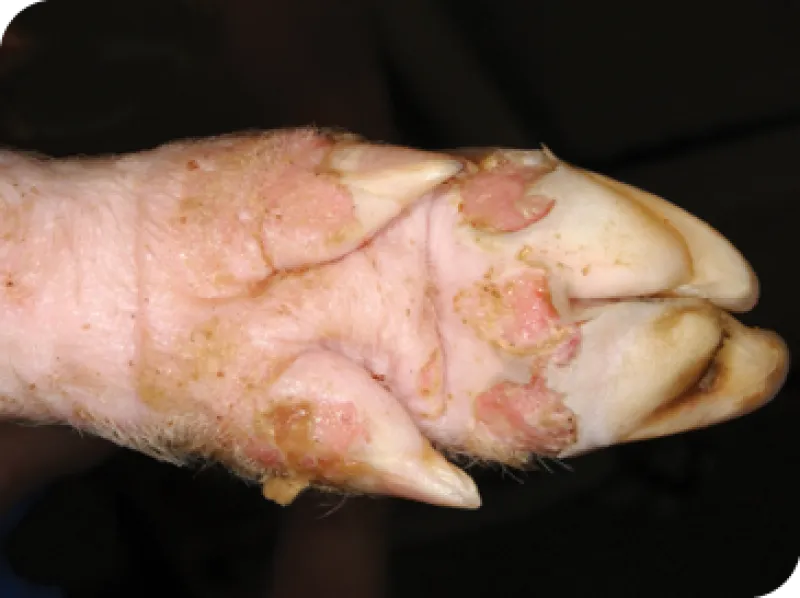

Signos de fiebre aftosa en cerdos domésticos

• Ampollas y llagas: Pueden aparecer ampollas en la boca o en la lengua, en los pezones y en las pezuñas. Estas ampollas pueden romperse y dejar erosiones crudas en el tejido. Las llagas dolorosas pueden provocar síntomas adicionales, como los siguientes:

• Cojera: Los animales pueden mostrar renuencia a moverse o mostrar signos de dolor al caminar.

Los autores desean hacer un reconocimiento al Laboratorio de Diagnóstico de Enfermedades Animales Exóticas del APHIS del USDA y al Servicio de Información Visual del Departamento de Seguridad Nacional (DHS) en el Centro de Enfermedades Animales de Plum Island (PIADC), el Centro para la Seguridad Alimentaria y la Salud Pública de la Facultad de Medicina Veterinaria de Iowa State University y Rajeev Ranjan, Dirección del Proyecto sobre Fiebre Aftosa, Consejo Indio de Investigación Agrícola (lesiones en los pezones) por el uso de las imágenes de cerdos y ganado domésticos infectados por el virus de la fiebre aftosa.